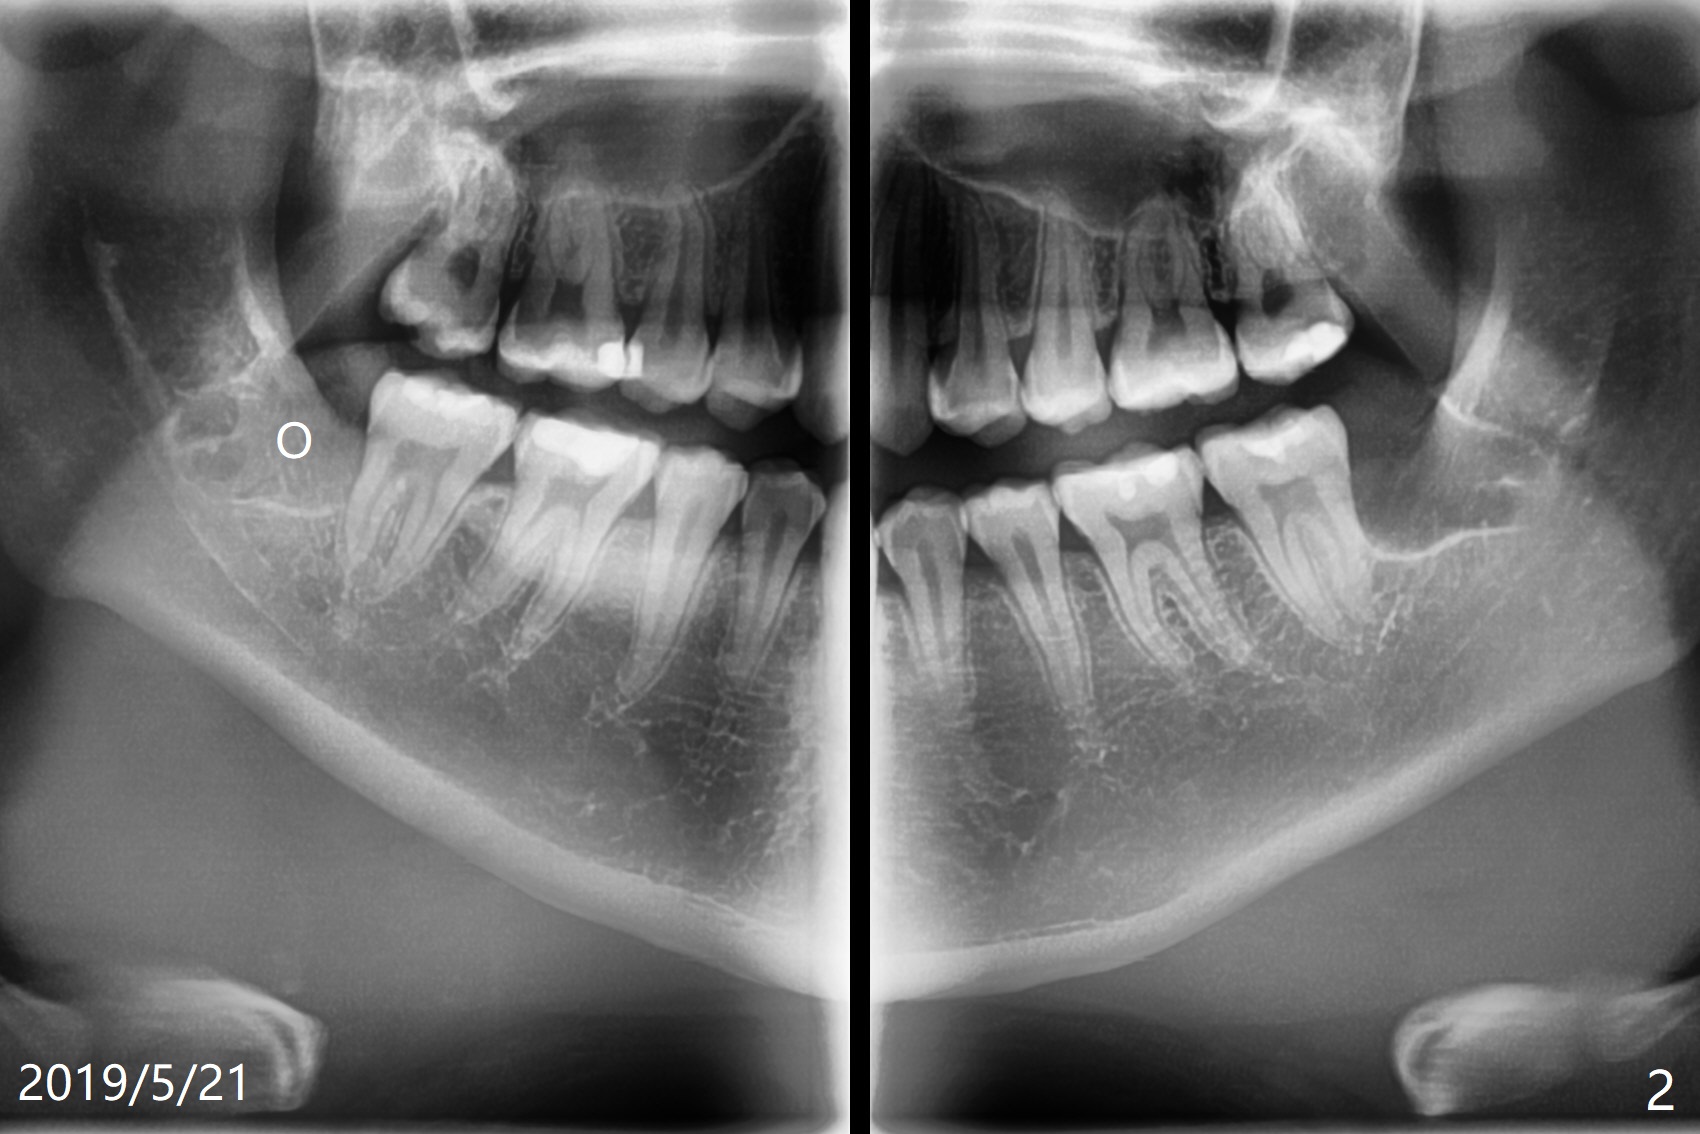

A 19-year-old woman requests extraction of #1,16,17 and 32 (Fig.1). The surgery is smooth except the fact that a surgical fissure bur tip is found to have been fractured without trace at #17. Before placement of Osteogen plug (Fig.2 O) and suture at #17, a regional panoramic X-ray for bitewing is taken. All of the sockets heal in 14 months (Fgi.3).